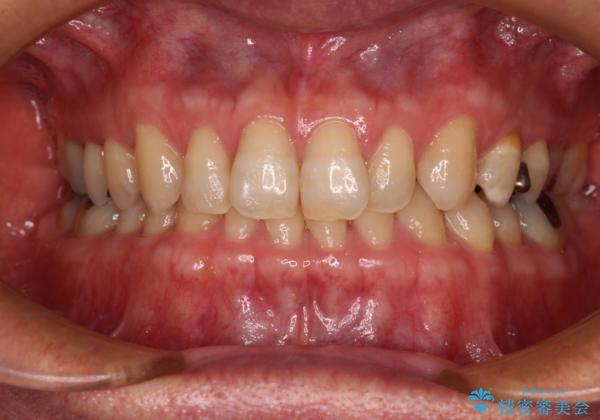

- 前歯のデコボコと隙間の空いた歯列を気にして来院された患者様です。

下顎前歯が隠れるほどのディープバイトにより、強い咬合力と突き上げで上顎歯列に隙間が空いている状態でした。

ディープバイトが改善され、睡眠時の食いしばりも緩和され、顎への負担が軽減されました。